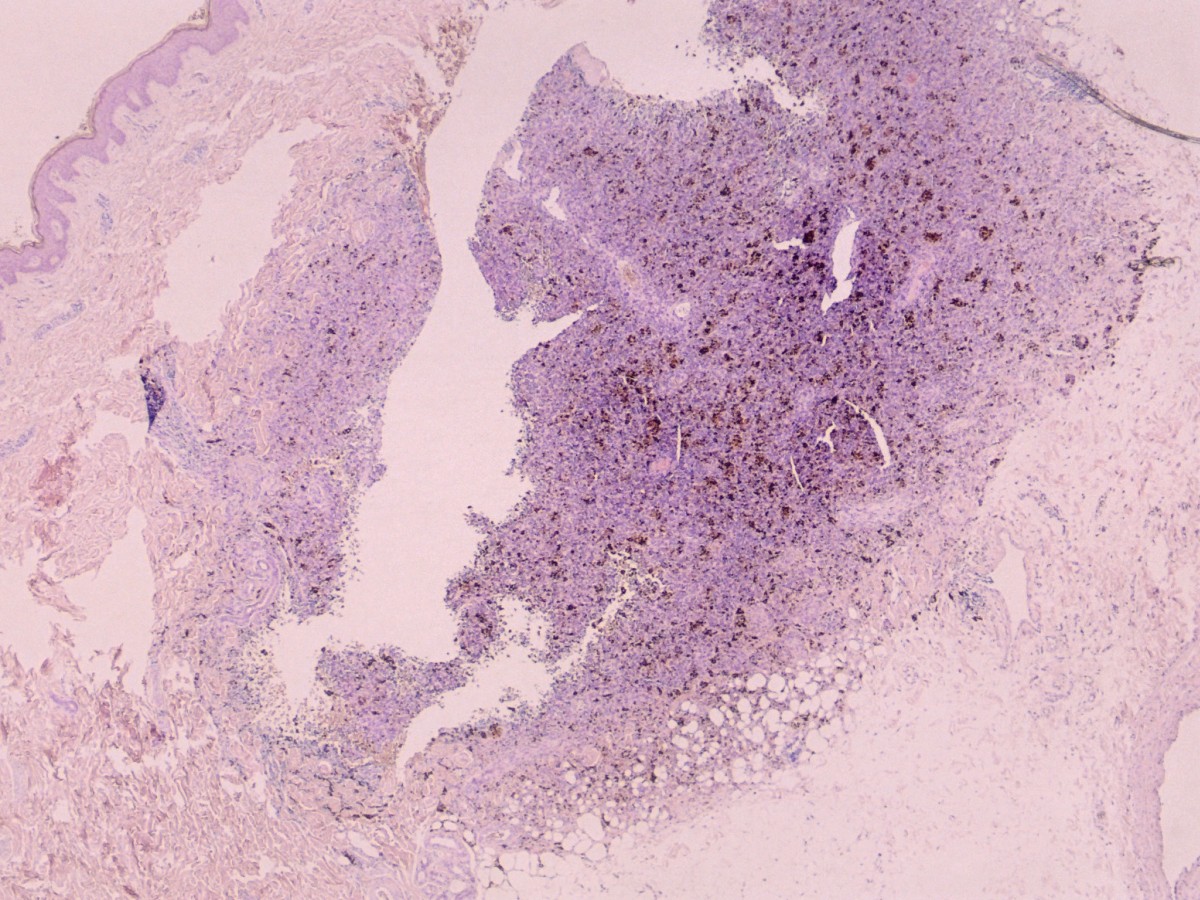

In de dermis, deels in bundels dicht opeengepakte fusiforme fibroblasten met licht vergrote, onregelmatige rond/ovale kernen, gerangschikt in een storiform patroon. Kern-atypie en (geringe) mitose activiteit. C34 positief. Er is meestal focaal veel ijzerpigment aanwezig. Naar de diepte is er uitbreiding in het vetweefsel. Zie ook de ingescande PA-coupe van de afdeling pathologie van de University of Toronto.

PA dermatofibrosarcoma ingescande coupe (zoom)

Bron hoge resolutie PA-foto: Kevin Kwee en Afdeling Pathologie MUMC. Klik op de afbeelding om in te zoomen.